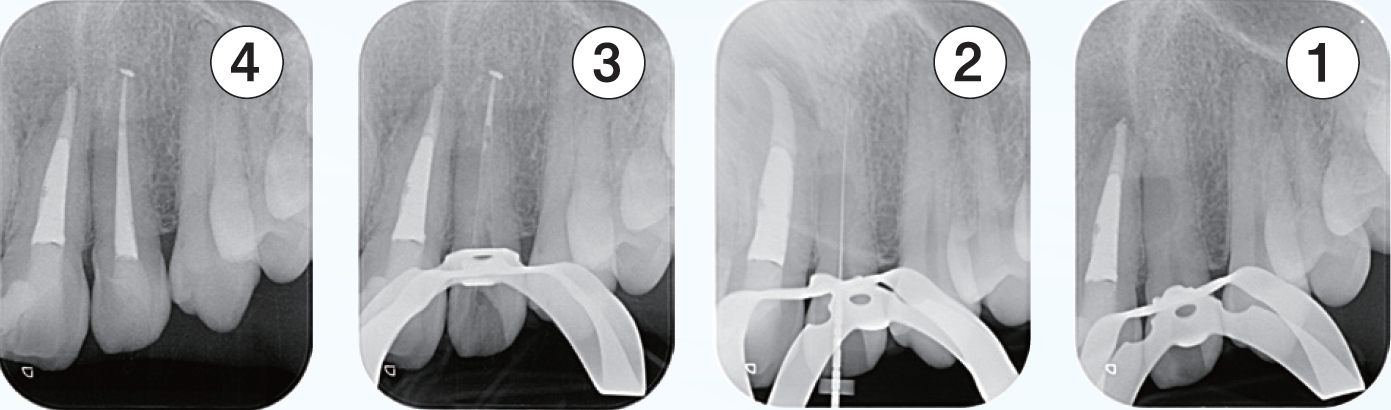

症例1は、根管処置後の打診痛を主訴に来院された症例である。

初診時のデンタルX線像を示す。レントゲン所見では根尖周囲組織に炎症を示す像を認め、その影響が上顎洞粘膜の肥厚の原因と推測されるレントゲン像である。

<症例1>●初診時年齢 31歳 女性 初診日2011/10/14

左上5番を他院で根管充填後、打診痛が消失しないので転院され受診患歯にはインレー修復がされている。根尖部は上顎洞と近接しており、上顎洞粘膜の肥厚も認められた

(症例1・①)根管充填の状態は比較的良好である。根管拡大・形成の3次元的評価のためCBCTを撮影。

CT像左上5番根尖部を中心として上顎洞粘膜の肥厚が認められ、根尖性歯周組織炎の影響が上顎洞まで及んでいると考えられた

根管処置後の修復が保存修復されて髄室開拡に制限があり、歯頸部周辺に存在する頬口蓋側に広がる髄角の形態が確認でき(症例1・②)、この部分に根管拡大不足の可能性を疑えた。根尖病変の原因として、頬口蓋的な根管拡大不足による起炎物質の取り残しによる感染が要因の一つであると診断した。より的確な予防形成を行うにあたり、器具操作の向上のため髄室開拡の修正が必要であると判断した。よって最終修復は歯冠修復による補綴修復が必要であると患者に説明し、承諾が得られたので再治療を行なった。

(症例1・②)

線で示した部分に髄角部の形態がそのまま残存していることが予測され拡大不足、未処置部分が存在すると判断した

根管充填後のレントゲン所見を示す(症例1・③)。術前と比較し、レントゲン上では上顎洞粘膜の肥厚も改善傾向が認められる。根尖病変の主原因がバイオフィルムであり、機械的な拡大形成は必須であるため根管を3次元的に捉えて処置することが重要である。デンタルX線では近遠心的な形態は確認することができるが、頬舌的な形態を確認することは偏心投影をしても難しい。CBCTは根管処置を行う上で非常に有益な情報を得ることができると考える(症例1・④、⑤)。

(症例1・③)

根管充填、支台築造後のレントゲン像術前と比較しレントゲン上では上顎洞粘膜の肥厚も改善傾向が認められる

(症例1・④)

術前と比較して頬口蓋方向に膨らんでいた髄角部の形態の変化が確認でき、未処置部分が減少していることが確認できる。上顎洞粘膜の肥厚も術前と比較し改善傾向にある

(症例1・⑤)根尖部のCBCT像

根尖部の開口部は3つ以上存在し、根管充填材が開口部を封鎖していることが確認できる